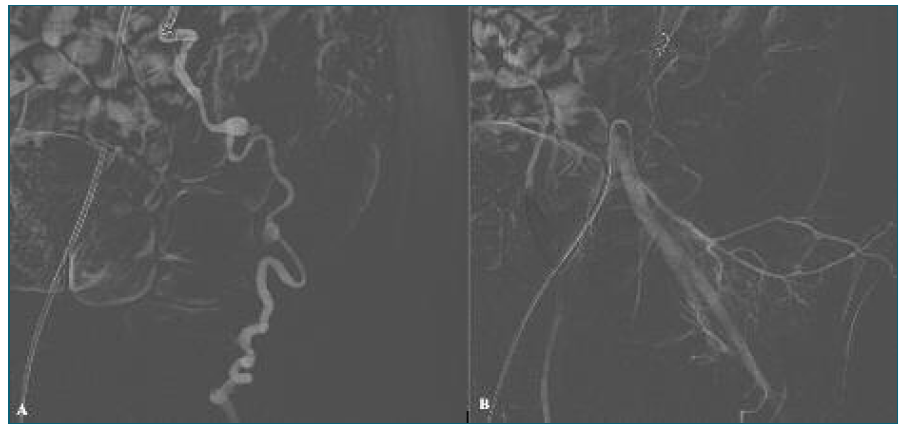

Initial laboratory tests revealed a hemoglobin drop from 11 g/dL in late pregnancy to 9.3 g/dL, suggesting mild postpartum anemia. A renal-bladder ultrasound and an abdominal X-ray imaging (Figure 1) were performed, excluding urinary and intestinal complications. Persistent pain along with an episode of lipothymia prompted an urgent abdominopelvic contrast-enhanced CT-scan, revealing a 19 cm retroperitoneal hematoma in the left flank and iliac fossa (Figure 2). Additionally, a 7 mm pseudoaneurysm in the LOA was identified as the source of intermittent hemorrhage (Figure 3A).

Figure 2 Abdominal-pelvic CT scan performed 2 days postpartum, showing a retroperitoneal hematoma measuring at least 12 × 13.4 × 19 cm (anteroposterior × transverse × longitudinal), localized in the left flank and iliac fossa. An enlarged uterus with a heterogeneous enhancement pattern results from normal postpartum changes.

Figure 3 (A) Three-dimensional CT scan reconstruction showing a 7 mm saccular structure in the LOA, consistent with an ovarian artery pseudoaneurysm. No active bleeding was observed at the time of image acquisition, though intermittent hemorrhage was suspected; (B) Diagnostic angiography confirming the OAA in the LOA with active bleeding proximally to the pseudoaneurysm. The yellow arrows represent the OAA identified in both imaging diagnostic tools.

Hemoglobin dropped to 5.2 g/dL within a few hours, and the patient was transferred to the ICU to immediate resuscitation with 1 L crystalloid, 1 gram of tranexamic acid, and 3 units of red blood cells. After consultation with the vascular surgical team, the patient was taken to the Angio-Suite for urgent TAE. Approaching the common femoral artery, the LOA was selectively catheterized, and a diagnostic angiography confirmed the pseudoaneurysm (Figure 3B), with active bleeding at its proximal segment. Embolization of the proximal LOA was performed with 3.0- and 4.0-mm micro-coils. In attempting to microcatheterize the distal LOA, a new bleeding episode was identified, requiring additional embolization with thrombin and a 6.0-mm micro-coil (Figure 4A). Post-embolization angiography of the left hypogastric and common iliac arteries confirmed successful occlusion of LOA. (Figure 4B). Post-TAE, the patient was transfused an additional unit of erythrocytes, achieving a hemoglobin level of 8.5 g/dL. The patient had an uneventful recovery and was discharged within 5 days.

Figure 4 (A) Using a Cobra catheter via the common femoral artery, the proximal segment of the LOA was accessed and embolization with micro-coil was performed (MReye® coils, 3.0- and 4.0-mm). Due to contrast leakage after catheterization of the distal LOA, additional embolization with thrombin and a 6.0-mm micro-coil was performed. (B) Post-embolization control angiography through the left hypogastric and left common iliac arteries showed no evidence of active bleeding, confirming successful occlusion of the LOA.